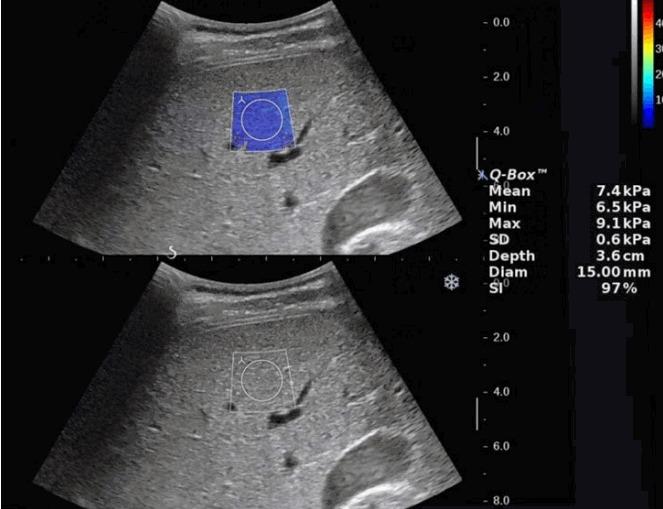

The purpose of this study was to evaluate the usefulness of the stability index (SI) in liver stiffness measurements using shear wave elastography (SWE) in children.

A total of 29 children and young adults (mean age, 16.1 years; range, 8 to 28 years; 11 boys and 18 girls) who underwent liver stiffness measurements using SWE under free-breathing and breath-holding conditions were included in our study. Ten SWE measurements were acquired in each of four groups: free-breathing and breath-holding, and with and without using the SI. The failure rate of acquisition of SI values over 90% was calculated in each group. To evaluate variability in the SWE measurements, the standard deviation, coefficient of variation, and percentage of unreliable measurements were compared. Intraobserver agreement and the optimal minimal number of measurements were calculated using intraclass correlation coefficients.

A failure to acquire SI values over 90% was observed in 17% of the scans in the free-breathing group and in 7% of the scans in the breath-holding group. In both groups, utilizing the SI led to a significantly lower standard deviation and coefficient of variation. When using the SI, the percentage of unreliable measurements decreased from 16.7% to 8.3% in the free-breathing group and 14.8% to 0% in the breath-holding group. With the use of the SI, intraobserver agreement increased and the optimal minimal number of repeated measurements decreased in both the free-breathing and breath-holding groups.

Utilization of the SI in the measurement of liver SWE in children reduced measurement variability and increased reliability in both free-breathing and breath-holding conditions.